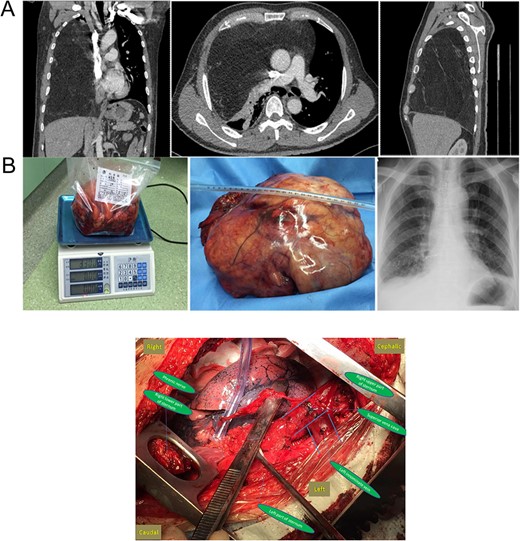

(A) Preoperative chest CT and (B) gross specimen and postoperative chest X-ray. Central Picture: “⊣ shape” incision and intraoperative surgical field after removing the giant mass.

The gross size of the tumor was 27 cm × 20 cm × 15 cm, weigh ~3.3 kg. And it was covered with a capsule (Fig. 1B). The cut surface appeared lobulated in shape and was pale yellow in color. The final pathological diagnosis was a well-differentiated liposarcoma. The patient experienced an uneventful recovery. Postoperative chest radiography showed a normal right lung (Fig. 1B).